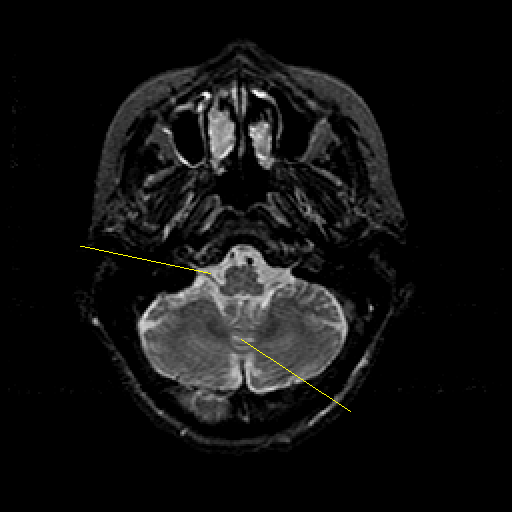

T2-weighted structural MR: Slice 11

Slice 11

Pointers

Labeled